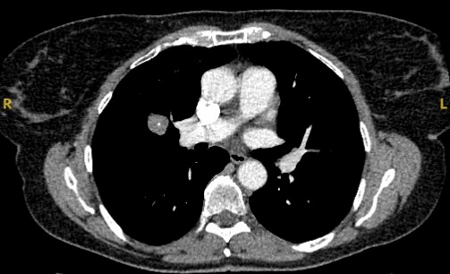

Solid nodules: volume doubling time of >600 days does not require follow-up, while a volume doubling time of <400 days, or clear growth defined as an increase in volume of 25% or more, suggests diagnostic investigations are required.[Figure caption and citation for the preceding image starts]: Computed tomography (CT) showing a right upper lobe spiculated solitary nodule within emphysema, in a current smoker with previous asbestos exposure. Note the visible pleural plaque on the left side. Resection histology revealed adenocarcinoma of the lungFrom the collection of Dr George Tsaknis, MD, PhD, FRCP(London), MRQA, MAcadMEd, PGCert; used with permission [Citation ends].